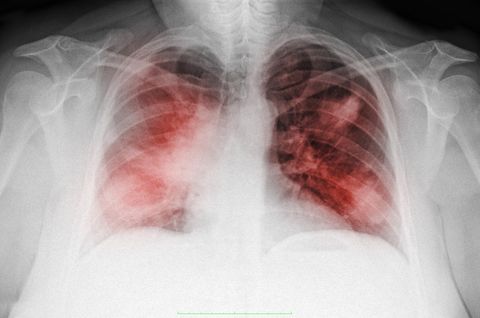

La neumonía es una infección que inflama los sacos aéreos de uno o ambos pulmones. Los sacos aéreos se pueden llenar de líquido o pus (material purulento), lo que provoca tos con flema o pus, fiebre, escalofríos y dificultad para respirar. Diversos microrganismos, como bacterias, virus y hongos, pueden provocar neumonía.

La neumonía puede variar en gravedad desde suave a potencialmente mortal. Es más grave en bebés y niños pequeños, personas mayores a 65 años, y personas con problemas de salud o sistemas inmunitarios debilitados.